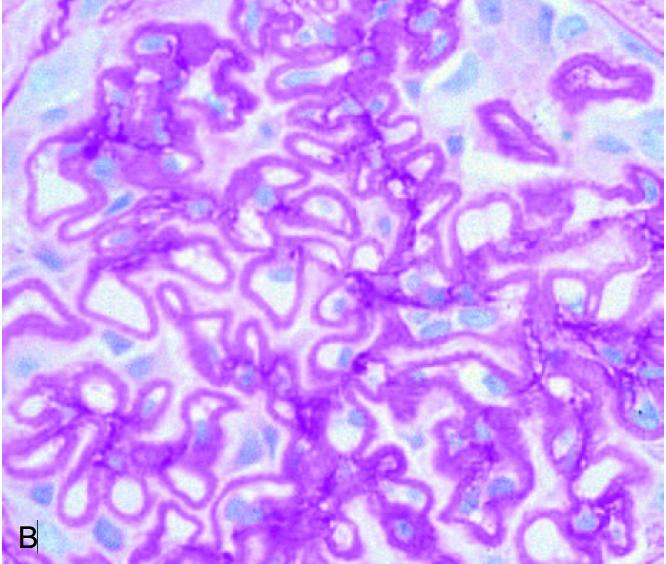

根据目前新的肾脏病理分类原则,狼疮肾炎(LN)被分类到「免疫复合物性肾小球肾炎(immune-complex GN)」。有时狼疮性肾炎可能与其他免疫复合物介导的肾小球肾炎混淆。而LN的组织学有如下特征可协助区分:

1,肾小球沉积物染色以IgG为主,可并有IgA、IgM、C3和C1q共同沉积,即所谓的「满堂亮」免疫荧光现象。

2,系膜、内皮下和上皮下区域可同时观察到肾小球免疫复合物沉积。

3,肾小球外免疫复合物沉积于肾小管基底膜、肾间质和血管。

4,肾小球内皮细胞中存在管网状包涵体。这些包涵体由核糖核蛋白和膜蛋白组成。

需注意,感染性心内膜炎、HIV、丙肝、链球菌感染后肾小球肾炎、门体分流术后的肾病活检也有「满堂亮」免疫荧光现象。HIV肾病也可有管网状包涵体表现。这需要结合临床进行鉴别。

2018年国际肾脏病理工作小组发表了初步的修改共识。第一步是对各种病变的定义予以明确和修正。像,内皮血管内增生(endocapillary proliferation)调整为「毛细血管内细胞增多(endocapillary hypercellularity)」 ……